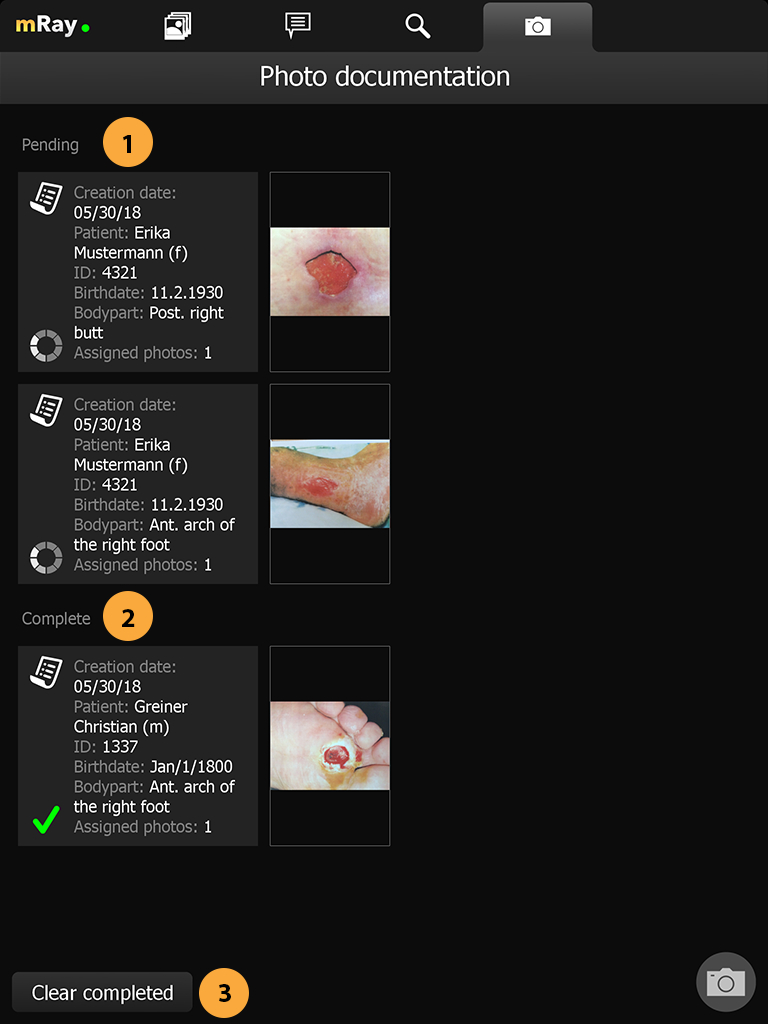

Wenn der Upload von Aufnahmen im Foto-Dok Workflow fehlschlägt, kann der Auftrag nun manuell wiederholt werden; Bilder und Auftragsdaten bleiben dabei möglichst lange erhalten

Neue Merkmale über Fotodokumentation Kamera hinzugefügt.